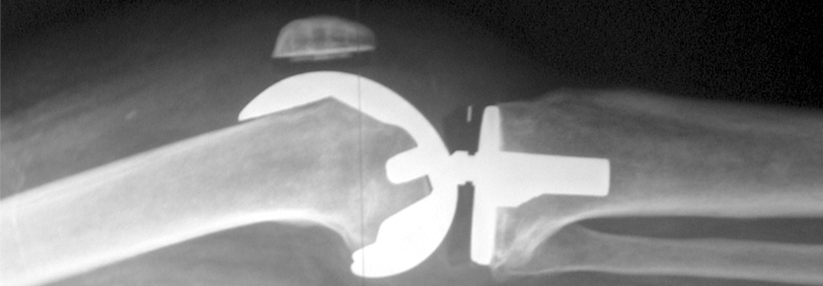

Eine ausführliche Anamnese und klinische Untersuchung reichen meist aus, um zu entscheiden, ob der Patient initial konservativ behandelt werden kann oder ob eine weitere Abklärung nötig ist. Falls es Anzeichen für einen strukturellen Schaden (z.B. Meniskus- oder Bandverletzung) gibt, sollte eine Bildgebung (Röntgenbild, Schnittbild­diagnostik) erfolgen. Wenn sich der Verdacht bestätigt oder weiterhin Unsicherheit besteht, sollte der Patient unverzüglich einem Facharzt vorgestellt werden.